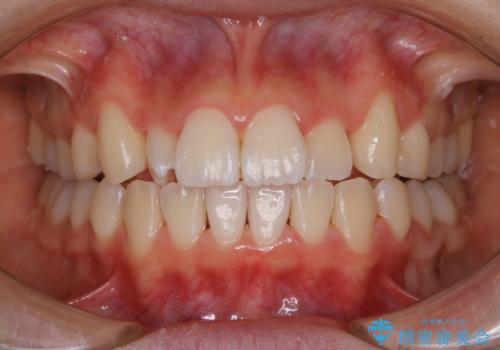

- インビザラインでの矯正治療中の方です。全体的に黄ばみ・黒ずみが気になるとのことでした。

PMTC60分コースを行いました。

PMTC(保険外治療)は、毎日の歯磨きで落としきれない汚れや、コーヒ、紅茶・タバコのヤニなどの着色も除去します。目には見えない歯と歯の間・歯肉の境目・インビザライン中はアタッチメント周囲などに残っているプラーク(歯垢)もしっかり取り除きます。PMTCでは専門的な機械や材料を使用して、徹底的に汚れを除去するため、虫歯・歯周病・口臭予防などにつながります。

またPMTCを行うことで、ご自身本来の歯の色になり自然な明るさになります。